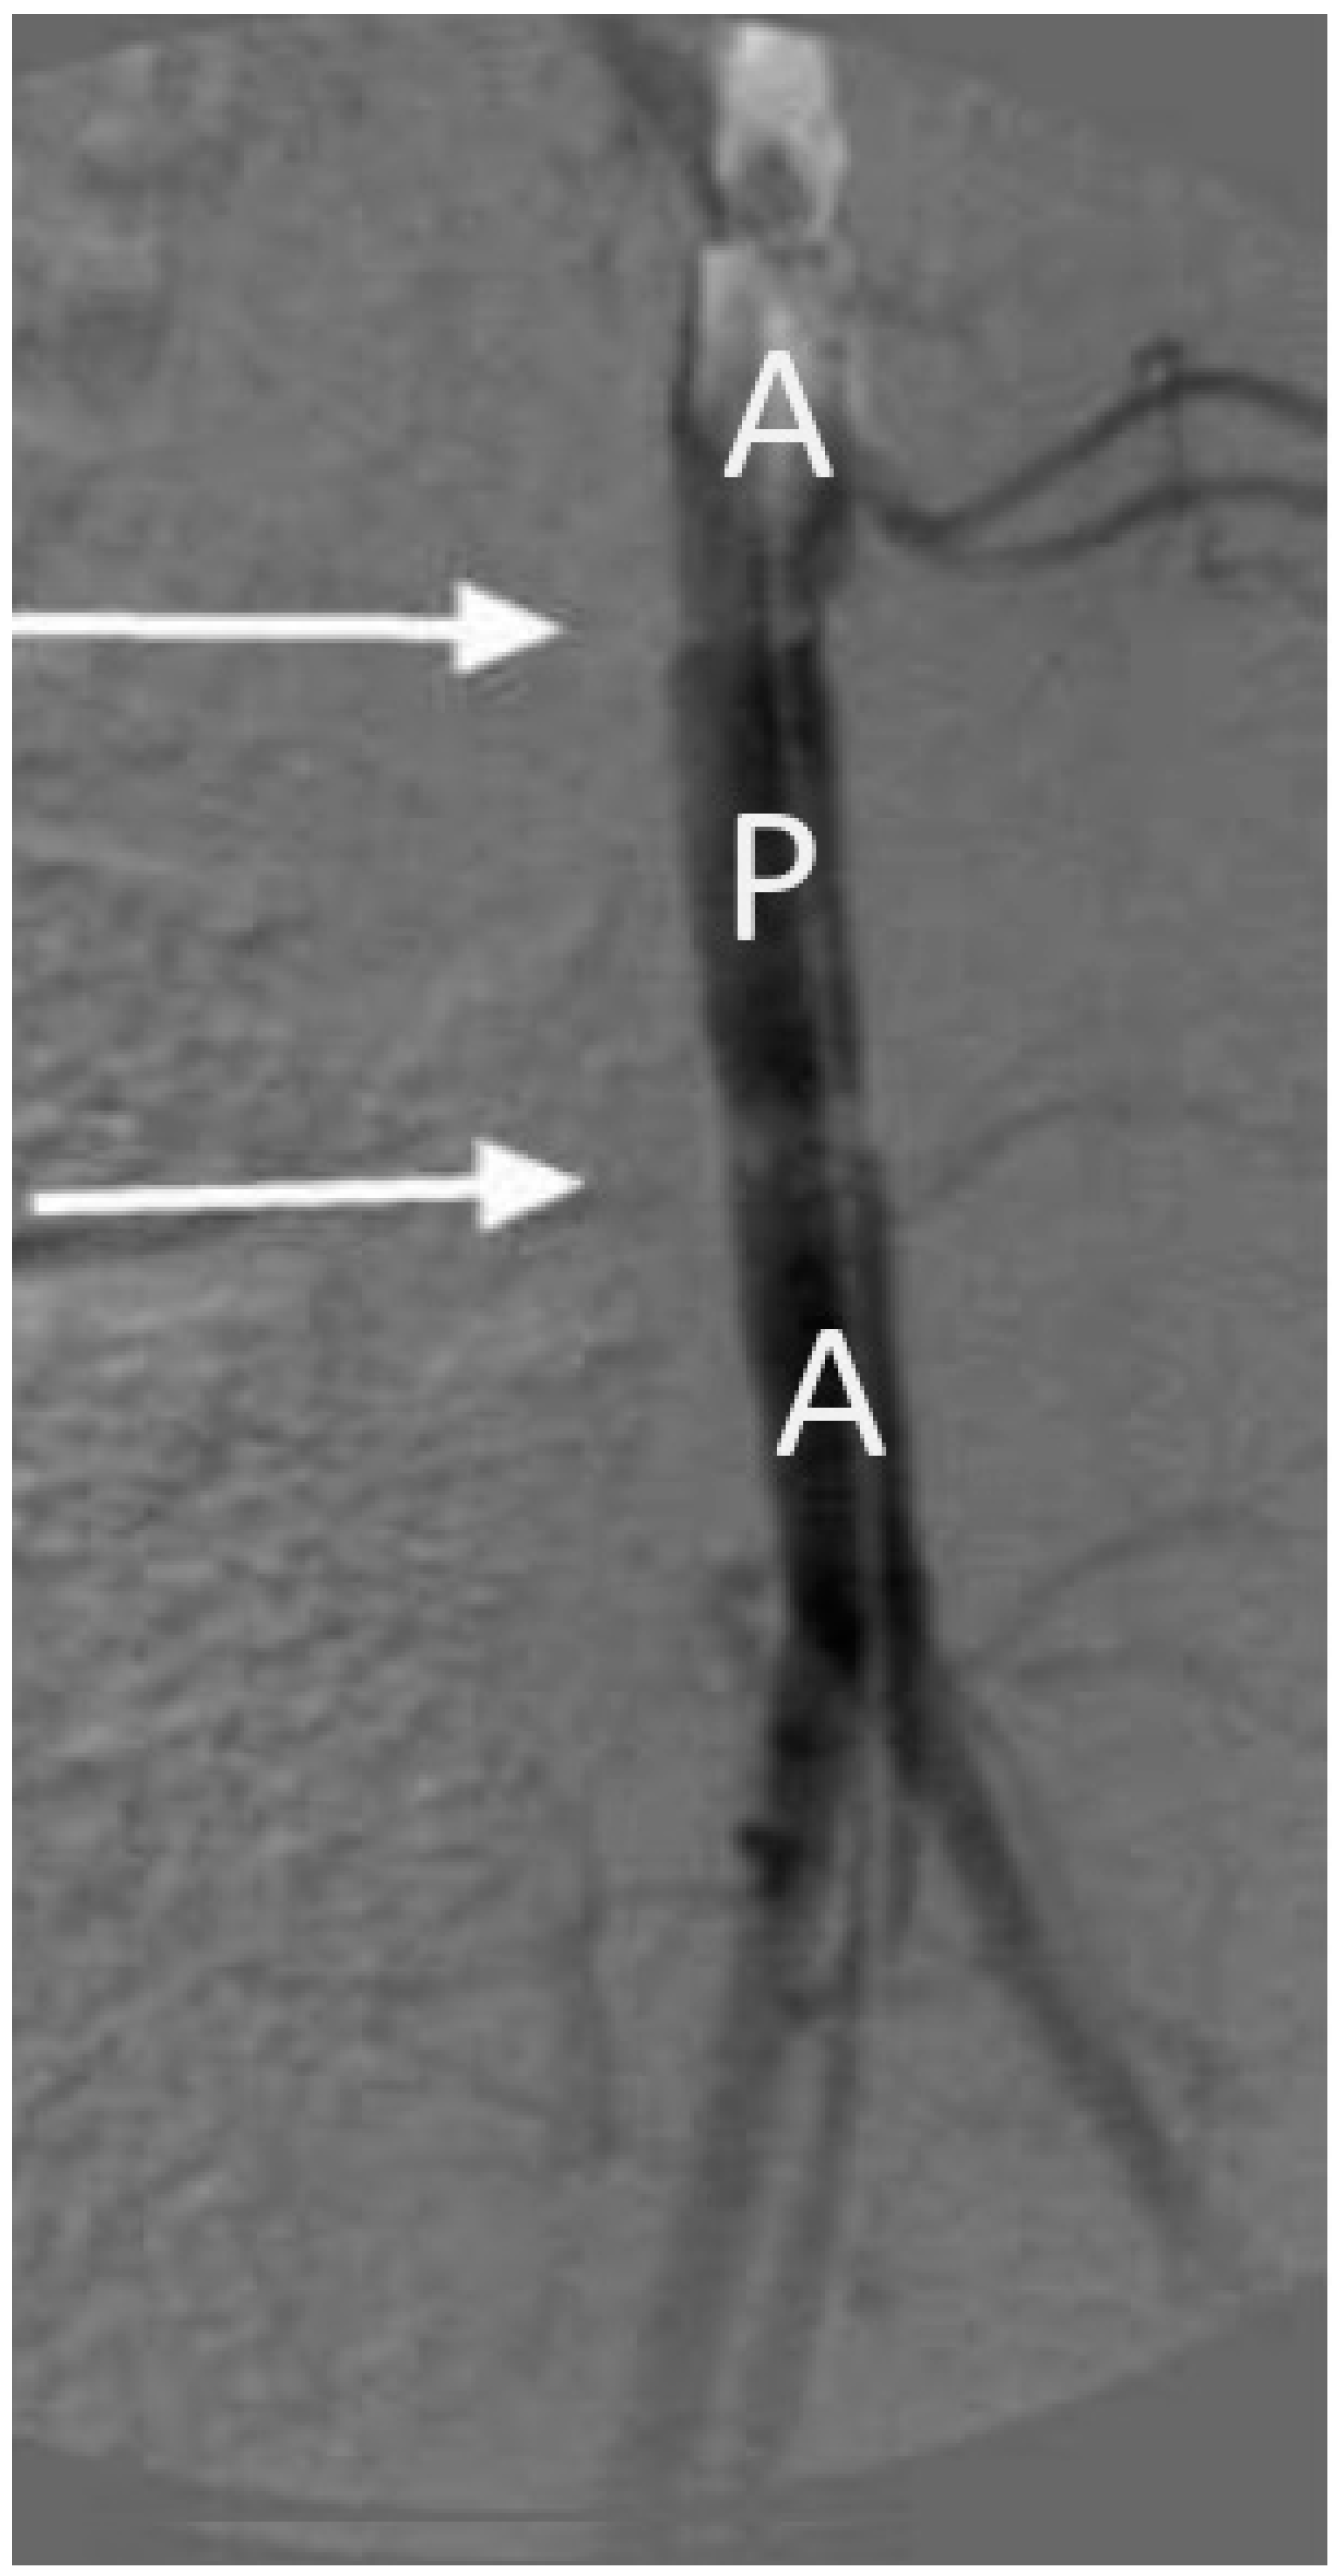

3.3. In Vivo Study of the of Vascular Prostheses Compliance

| Sample | Compliance, %/100 mmHg | |

|---|---|---|

| 3 Days | 30 Days | |

| Native aorta | 29 ± 1 | 24 ± 1 |

| BVP | 28 ± 1 | 22 ± 1 |